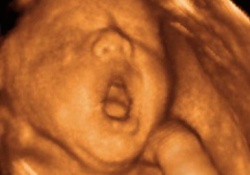

Появление в арсенале акушеров такого мощного диагностического средства как исследование с помощью ультразвука привело к новым открытиям. На протяжении многих лет ученые спорили, зевает ли плод в материнской утробе – наконец, ответ был получен.